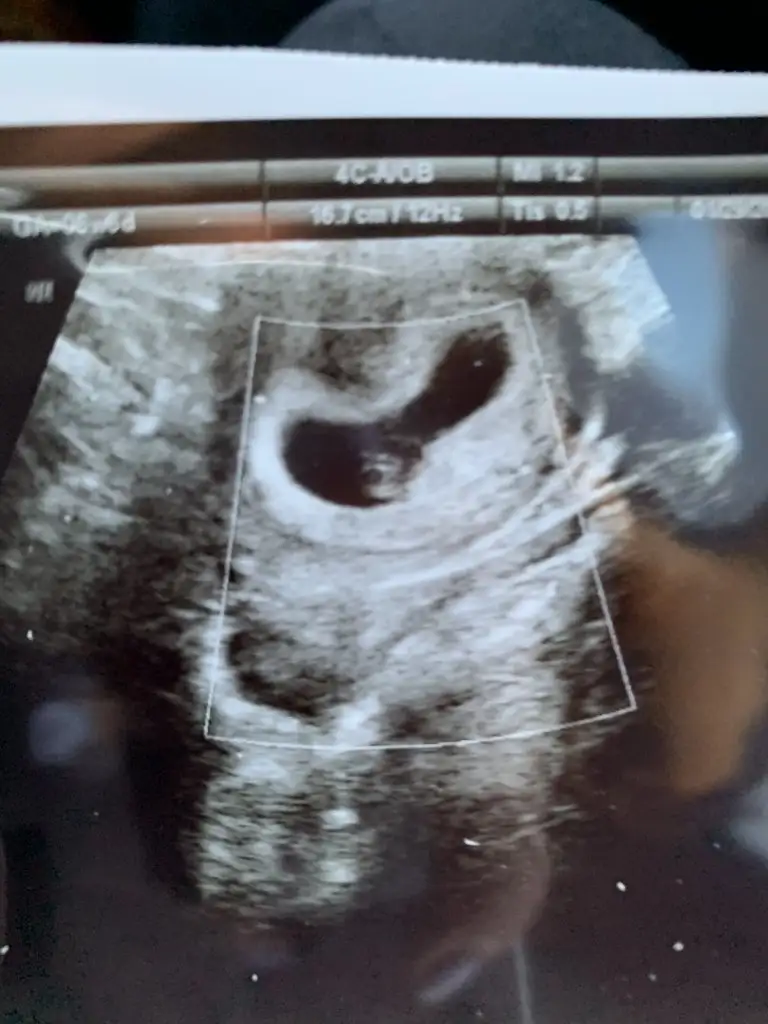

Merhaba arkadaşlar dünden beri yazdıklarınızı okuyorum yeni bitti.Rabbim hepimize de sağlıkla kucağımıza almayı nasip etsin.Benim 8 yaşında bir oğlum var sonrasında 4 kaybım var çok yaşadım o stresi bebeğin kalp atışı yok dediler hep.Rabbim kimseye yaşatmasın.Şimdi yine hamileyim bu defa çok şükür kalbini de duydum ama stresim yine bitmedi arada kahverengi lekelenmem oluyor.Pazartesi acile gittim bebek iyiydi ama leke gördükçe ben stres oluyorum.Yarın tekrar doktora gideceğim inşallah güzel ilerliyoruzdur